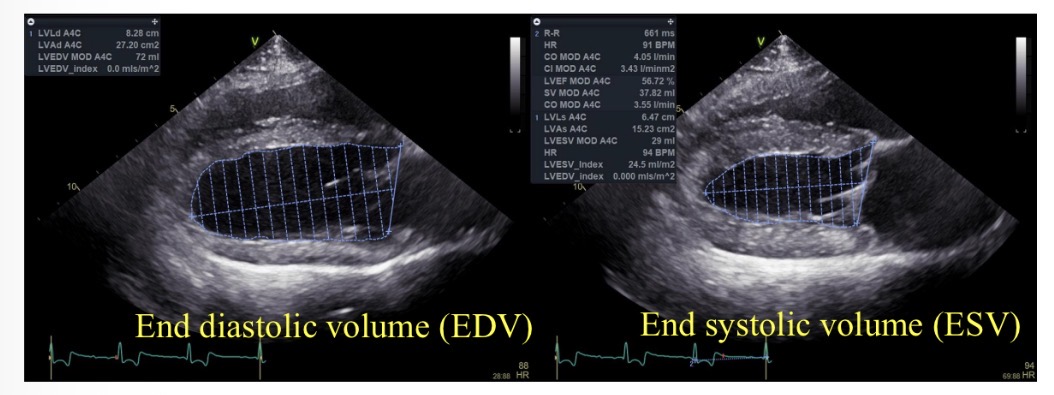

Ejection fraction (%) equation

((EDV-ESV) / EDV) x 100

Normal ejection fraction

>50%

Index of sphericity for LV equation

LV length in diastole / LV width

Index of sphericity for LV normal value

>1.7